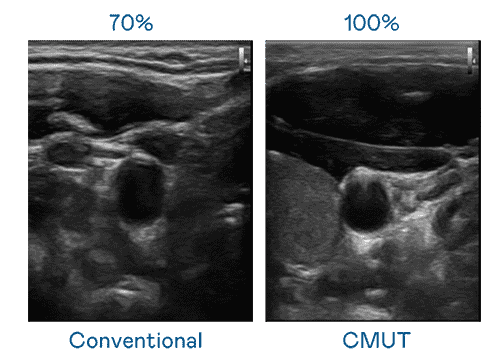

CMUT 技术是一种用电容式微机电元件来产生超音波讯号的技术。。与传统 PZT 压电式技术相比,,,CMUT 频宽增加 30%,,,更宽频的超音波讯号让影像解析度大幅提升,,是实现高影像品质医疗超音波扫描、、、促进精准医疗发展的关键技术。。。

超音波影像的解析度高低,,,,首先取决于探头能发出的讯号频宽。。。。巨星国际 CMUT 可提供高清晰的超音波讯号,,,提供高频宽、、、高灵敏度、、、、影像纹理细节更高的超音波影像,,协助医护人员缩短影像判读时间及利用精准的医疗影像进行诊断。。。。